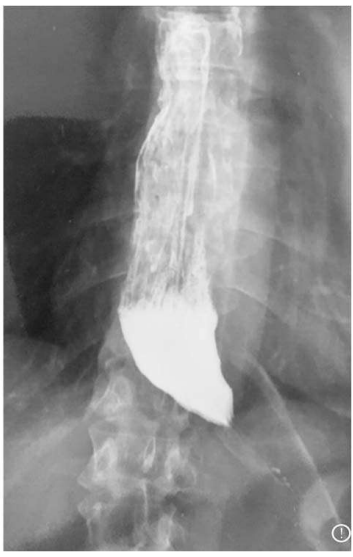

Considerando o exame acima apresentado, assim como seus achados, é correto afirmar que o mais provável sintoma do paciente seria